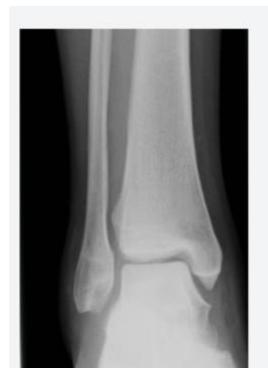

A 17-year-old male had a high ankle sprain followed by pain in his leg. X-ray films were obtained. According to the attached X-ray, which structure has been injured?

- B. Syndesmosis ligament

A 23-year-old male injured his ankle after a twisting ankle injury 2 days back. What is the most likely pathology based on shown x-ray?

Management Question: What is the management of the finding in the image?

- A. Screw fixation for syndesmosis injury

Answer 1: Ankle fracture (Suprasyndesmotic fracture in distal fibula type C with medial malleolus fracture)

Answer 2: ORIF by plate in fibula and syndesmotic screw, and screw for medial malleolus fixation

- 1: Ankle fracture (transyndesmotic fracture in distal fibula type B and medial malleolus fracture)

- 2: Open reduction internal fixation by plate in fibula and syndesmotic screw and screw for medial malleolus fixation

General Ankle Fracture

Diagnosis: Ankle fracture Mechanism: Twisting injury Common in: Old people